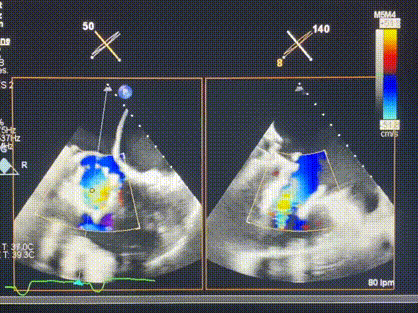

術后DSA顯示Lux-Valve Plus與Tendyne和ICD無相互影響

術后超聲顯示僅殘余微量瓣周漏